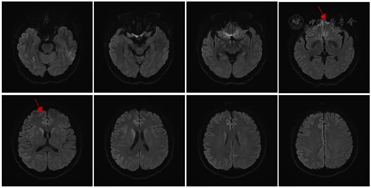

患者转院后表现查体:双肺呼吸粗,可闻及湿性啰音,余心腹系统等查体较前无明显变化。神经系统检查:无反应觉醒状态,不语,高级皮层功能检查不合作,颈强直,四肢肌张力高,双下肢腱反射(+++),右侧Babinski’s征(+),余查体不配合。患者头颅MRI、脑电图检查结果如图2,图3所示。脑脊液CSF结果显示:生化、常规、脑脊液病原学检查、自身免疫性抗体检查未见明显异常;脑脊液14-3-3蛋白阳性,朊蛋白(PRNP)基因突变阴性。

本例患者脑电图呈现有"周期性三相波",脑脊液中14-3-3蛋白阳性,头颅核磁影DWI显示有大脑皮质呈典型"花边征"及结合患者快速进展的临床症状考虑很可能为克雅氏病即Creutzfeldt-Jakob病(CJD)。

最后CJD典型辅助检查表现出现在不同的疾病时期,对临床甄别本病造成了一定困难。目前,CJD的确诊需要在死后或活检获得的脑组织中检测异常折叠的、CJD特异性蛋白酶耐药朊蛋白(PrPCJD),由于组织活检有感染病毒风险且活检程序繁琐、具有创伤性,因此,临床上对CJD的诊断往往具有挑战性。临床医生可以通过无创检查即脑MRI扫描、脑电图和脑脊液检查来协助诊断。头颅MRI:最早变化可出现在发病后1个月,并发生于脑电图及脑脊液出现异常结果之前;其敏感度及特异度可达到100%[1],少数患者早期可无异常改变。MRI的DWI相上可见对称或不对称性皮质"缎带征"或"花边征",基底节区(尾状核、壳核、丘脑枕)高信号对CJD早期诊断具重要意义[12]。FLAIR图像上双侧丘脑枕及丘脑背内侧的异常高信号为"丘脑枕征"和"曲棍球征"[1,5]。脑电图的早期敏感性一般但特异性较高,脑电图早期主要表现为非特异性弥漫性慢波及额部节律性6活动,中期则出现特征性的周期性尖慢复合波(为CJD标志性改变),至晚期则再次呈现非典型特征表现为类似昏迷状态的慢波及低电压活动[13]。本例患者在我院住院期间因配合度差未完成脑电图,故减少了诊断参考依据。最后对于脑脊液检查方面,随着病情进展,脑脊液蛋白数增加,目前唯一纳入WHO诊断标准中的分子蛋白是脑脊液中14-3-3蛋白。利用免疫方法检测脑脊液中14-3-3蛋白,在一定范围内该蛋白增加与患者典型临床表现增加呈正相关[14]。